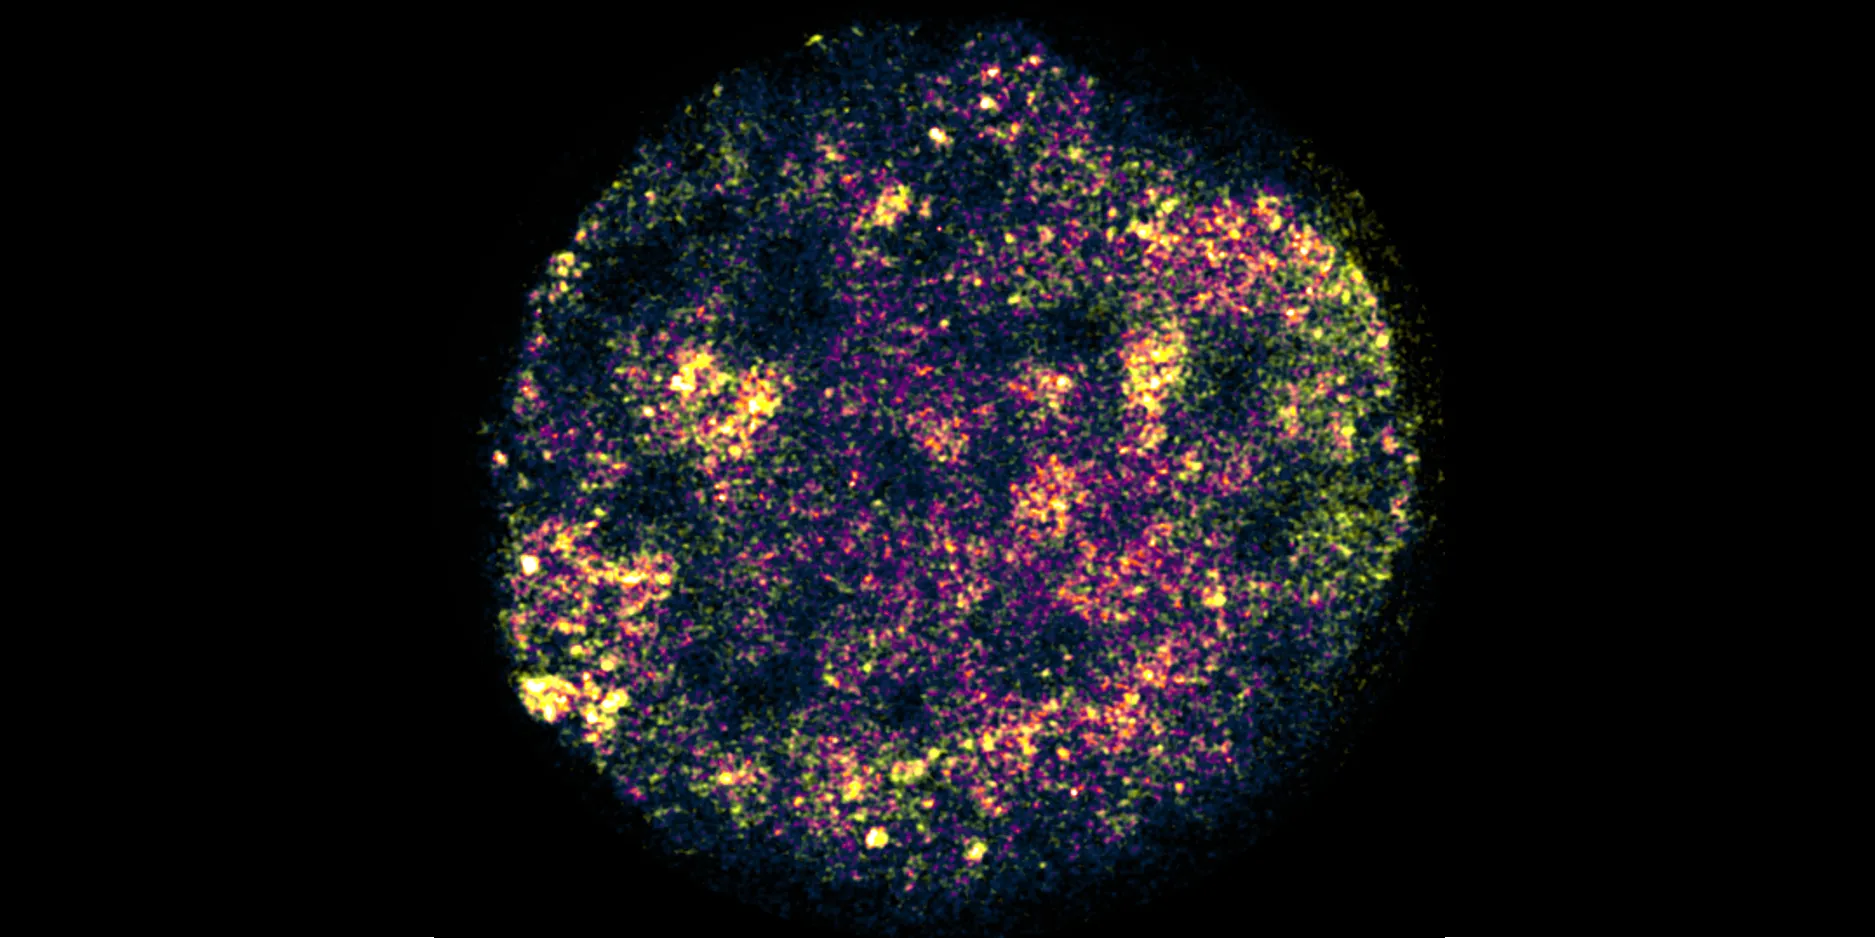

Since the human genome was first sequenced in 2003, research has mainly focused on parts of DNA that contain instructions for making proteins – the fundamental building blocks of all organisms. However these account for only two per cent of the three billion letters of the human genome.

Once thought of as ‘junk’ DNA, experts now believe that the dark genome has a crucial role to play in the development of a number of diseases, including cancer, by controlling how, when and where genes are switched on or off.

Image Credit: Julia Auer